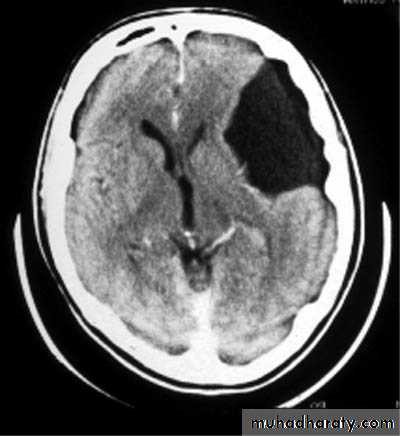

Sylvian Fissure Arachnoid Cyst

Investigations:

CT Brain

MRI Brain